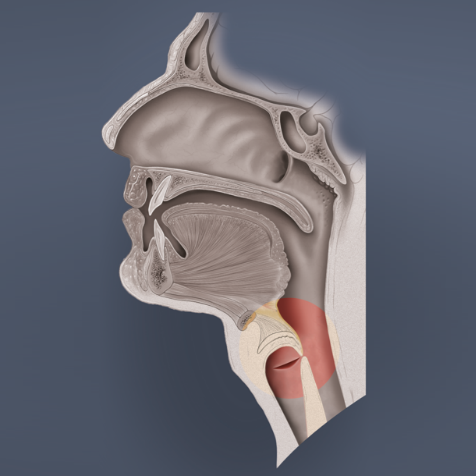

Zunächst ein bisschen Anatomie:

1. Am Druckausgleich beteiligte Organe bzw. Körperstrukturen

Bei jedem aktiven Druckausgleich wird „Luft“ durch Hohlräume in das Mittelohr bewegt.

Luftgefüllte Hohlräume:

- Lunge

- Mundhöhle

- Nasen-Rachenraum

- Mittelohr

Am Druckausgleich beteiligte Organe:

- Glottis (Stimmritze, engl. glottis)

Die Stimmritze stellt den Hohlraum zwischen den am Stellknorpel befestigten Stimmbändern dar und ist mit der Lunge und der Mundhöhle verbunden.

- Zunge (engl. tongue)

Die Zunge spielt eine wichtige Rolle beim Druckausgleich, denn sie kann die Mundhöhle an verschiedenen Positionen in einen vorderen und hinteren Bereich unterteilen. Dies wird später bei den „Stimmübungen“ klarer.

- Weicher Gaumen (Palatum molle, engl. soft palate)

Der weiche Gaumen ist Teil des Mundhöhlendaches und die Fortsetzung des harten Gaumens. Er besteht aus der Uvula (dem sogenannten Zäpfchen) und dem Gaumensegel (Velum palatini). Um das Gaumensegel liegen drei kleine Muskeln. Zwei davon, nämlich der Muskulus tensor veli palatini und der Muskulus levator veli palatini, werden später nochmals gesondert erwähnt – also merken! Der gesamte weiche Gaumen spielt eine maßgebliche Rolle beim Druckausgleich, da er die Mundhöhle mit der Nasenhöhle verbindet.

- Eustach’sche Röhre (Tuba auditiva, engl. Eustachian tube)

Die Tube ist eine 30 – 35 mm lange, mit Flimmerepithel ausgekleidete, Röhre, die das Mittelohr und den Nasenrachenraum verbindet. Ohne eine ausreichende Belüftungsfunktion ist der Druckausgleich unmöglich, da dies der einzige Zugang zum Mittelohr ist. Im Normalzustand ist die Tube geschlossen, öffnet sich jedoch beim Schlucken, Gähnen oder bestimmten Lauten und natürlich beim Druckausgleich.

- Epiglottis (Kehldeckel, engl. epiglottis)

Der Kehldeckel ist eine mit Schleimhaut überzogene Knorpelplatte und verschließt beim Schlucken den Weg zur Lunge. Passiert dies nicht oder unvollständig, verschlucken wir uns und bekommen etwas „in den falschen Hals“. Die Epiglottis ist beim Druckausgleich nur beteiligt, wenn dieser durch Schlucken bewerkstelligt wird.